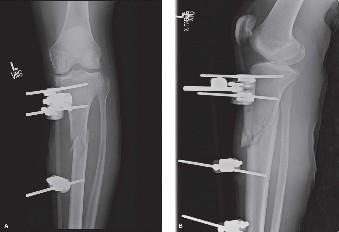

A 55-year-old man is involved in a high-speed motorcycle crash. Upon presentation to a level 3 trauma center,…